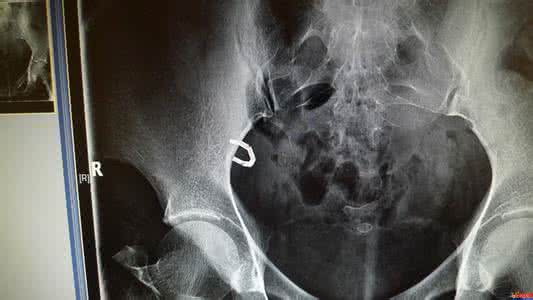

脱环多见于第1年,尤其以前半年多见,时间久了,子宫对环已适应,脱落机会减少,故放节育器后的妇女,要按期随访,可用X线或B超检查,以便及时发现脱环。